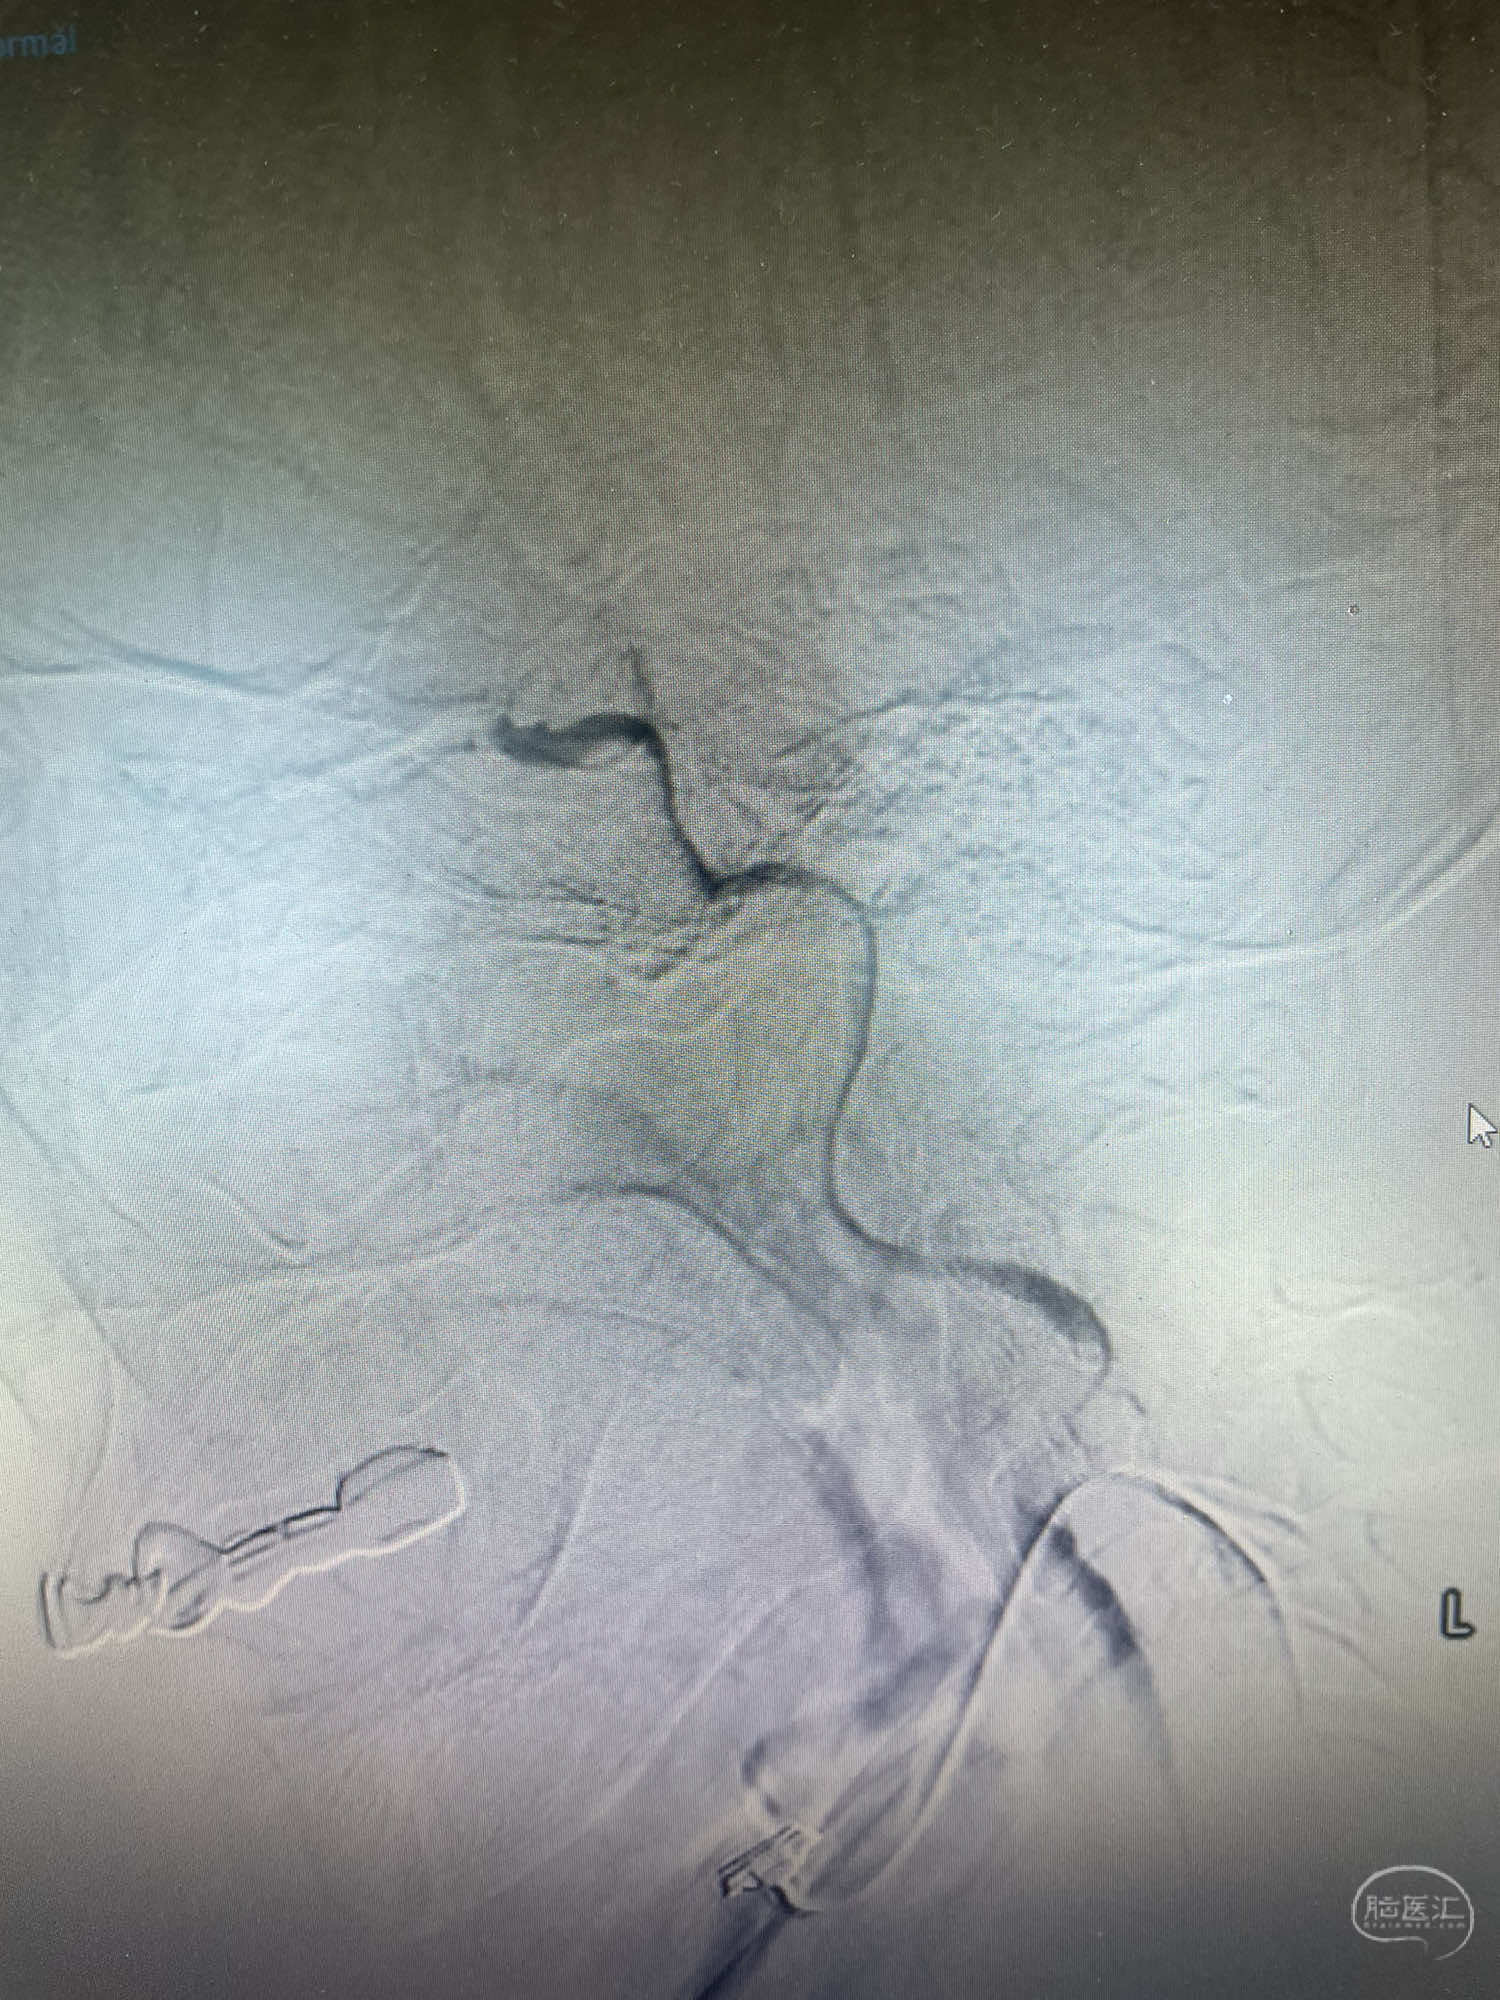

术后复查脑血运重建满意